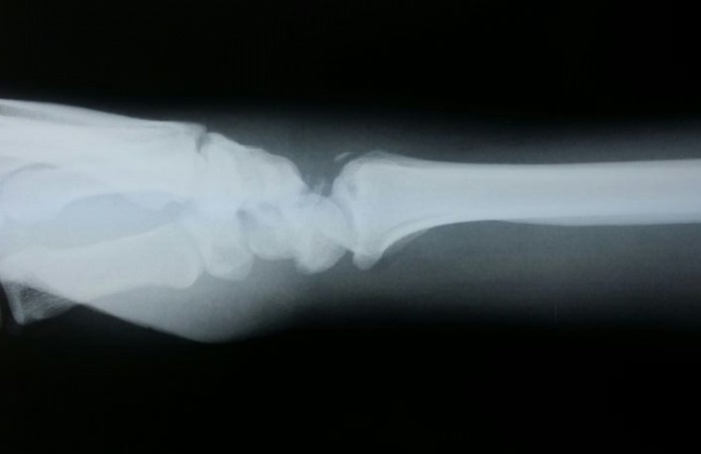

Plain X-rays, asking for scaphoid views and should include a posteroanterior (PA) and lateral of the wrist, ulnar deviation PA and supination oblique views. A CT scan is suitable for fracture morphology, but should only be requested by the treating surgeon. MRI is the most sensitive investigation for picking up occult scaphoid fractures. If a scaphoid fracture is suspected clinically, but the X-ray does not show a fracture, then the patient must be placed in a backslab and seen again after 10-14 days for a repeat examination and X-ray. If earlier confirmation is required, then an MRI scan should be performed.